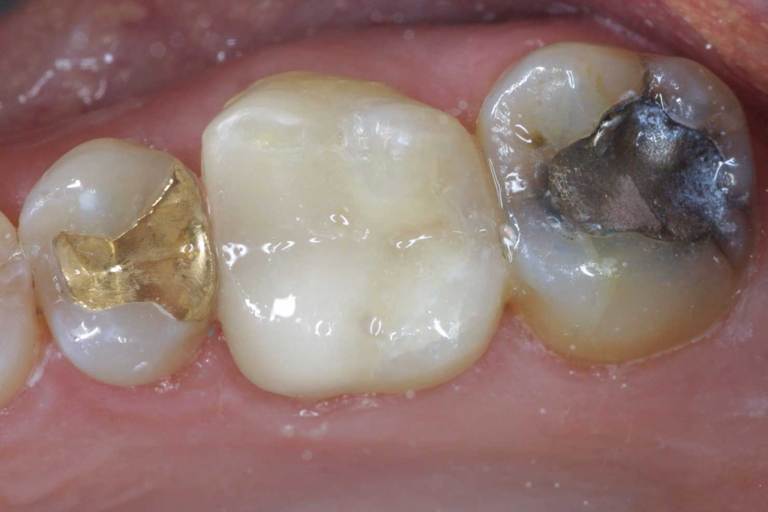

Tooth-colored fillings, white fillings and composite resin fillings are all names for the high-strength, natural-looking fillings that can be placed today instead of silver or gold (also known as amalgam fillings). No matter what the name, The Max Dental Center will know just what you're talking about when referring to this natural-looking filling.

Composite fillings are today's modern filling choice. They are made to match your tooth's natural color to make them virtually invisible to notice and are placed onto the tooth by bonding the filling material to the tooth so they do not have the unlikely chance of falling off. Many patients choose to replace their old silver and gold fillings with composite fillings.

White fillings are made from a high-strength composite resin that can be easily color-matched to your natural tooth making it nearly invisible to you and anyone else. Unlike silver and gold fillings, composite tooth-colored fillings actually bond to the tooth which means they support the surrounding tooth structure, which helps to prevent breakage and insulate the tooth from excessive temperature changes. You are much less likely to have a composite filling fall out which is a common issue with metal fillings.